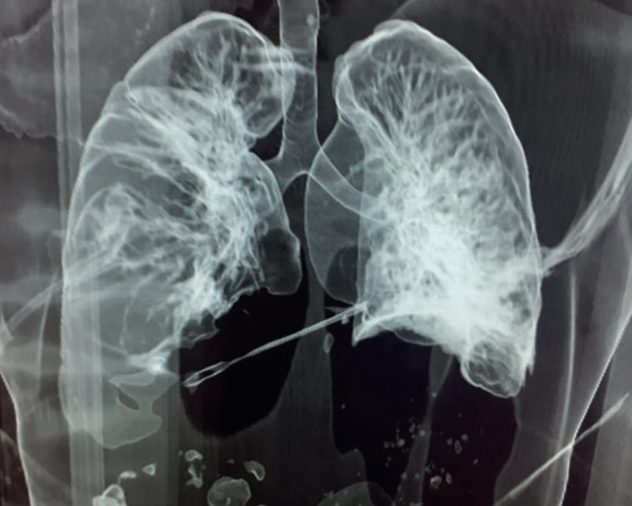

Se tomó radiografía de tórax antero posterior que mostraba hemoneumotórax derecho ,por lo que se realizó pleurotomía. TC de tórax que mostró un leve hemomediastino e “imagen densa con endurecimiento del haz”. (Fig. N°2-4) Se planteó TPC y se realizó toracotomía de urgencia, encontrando hoja de cuchillo que transfixiaba todo el ventrículo derecho, posterior a su extracción, por exanguinación y arritmia cayó en PCR irreversibleDOI: http://dx.doi.org/10.35687/s2452-454920240052110